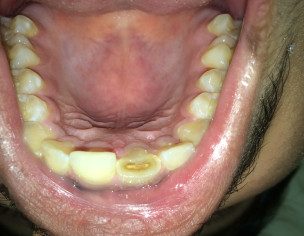

Asking for Self, Male, 19 years old, 121 Nadeem Park Kotlakhpat Lahore

Sir mera aik dant tut gya tha fornt wala but mujhy kch nei hua ya last year or is year is dant mn or isky sth walay dant mn bht resha par gya hai jiski wja sy mujhy bht takleef hai plz give me any medicine plz plz plz

aap ko root level pay infection ho gae hai medicine without history nahe day saktay apnay qareebi dentist say fori rabtaa karain

Attach Photo here: